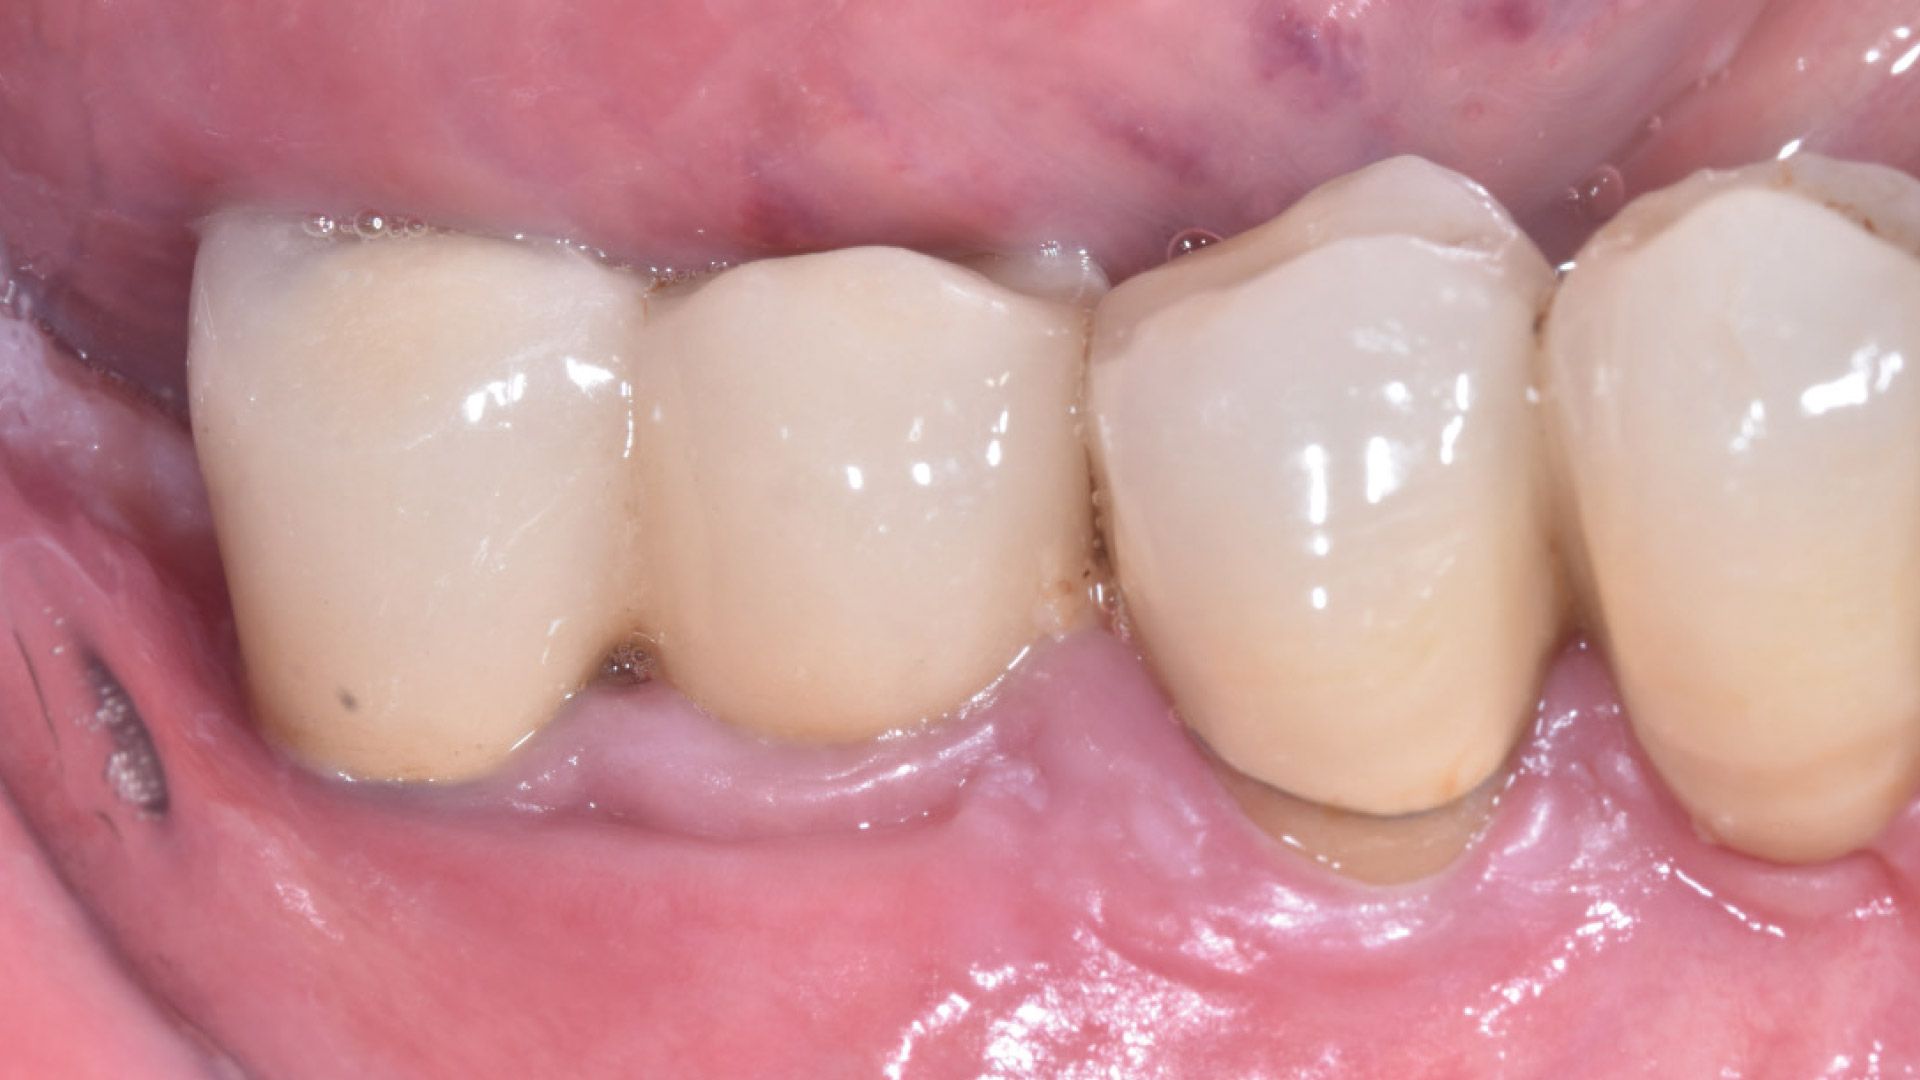

Lo studio è stato condotto presso studi dentistici privati con sede a Roma e Como. Sono stati reclutati 27 pazienti e divisi in gruppo 1 (applicazione di gel a base di clorexidina nei siti con mucosite perimplantare), gruppo 2 (applicazione di gel a base di Ozono) e gruppo 3 controllo (senza utilizzo di gel topici). Al baseline (T0) si è proceduto a valutare lo stato clinico dell’elemento implantare attraverso foto e radiografie periapicali, è stato poi rilevato l’indice di sanguinamento (Gengival Index) e successivamente è stato eseguito un debridement sub-gengivale tramite l’utilizzo di Glicina. Per il trattamento domiciliare ai pazienti sono stati consegnati gel a base di Ozono o di Clorexidina al 1% da applicare nei siti tramite lo scovolino. A T1(a 1 mese da T0) e a T2 (a 3 mesi da T0) sono state ripetute le stesse valutazioni e le stesse manovre professionali (Figg. 1a-6).

Figg. 1a, 1b - Gruppo 1: elemento 46, immagine acquisita a T0; Fig. 2 - Gruppo 1: elemento 46, immagine acquisita a T1; Fig. 3 - Gruppo 1: elemento 46, immagine acquisita a T2; Figg. 4a, 4b - Gruppo 2: elemento 11, immagine acquisita in T0; Fig. 5 - Gruppo 1: elemento 11, immagine acquisita in T1; Fig. 6 - Gruppo 2: elemento 11, immagine acquisita in T2.